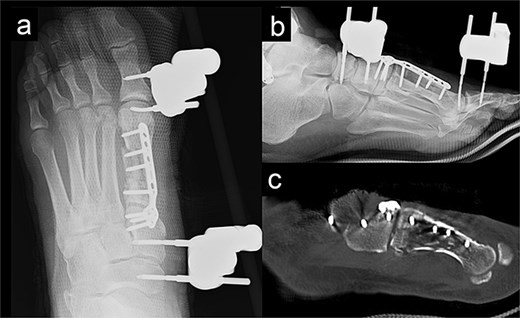

We performed surgery in two stages, owing to the poor condition of the skin. In the first stage, we performed screw fixation for the tibial pilon fracture and plate fixation for the distal fibular fracture. For the first-metatarsal fracture, half pins for external fixation were inserted into the first proximal phalanx, first metatarsal, medial cuneiform, and navicular bone. The external fixator (The Small External Fixation System, Synthes, Oberdorf, Switzerland) was stabilized with the first reduction in the metatarsal shortening deformity (Fig. 2). One week later, the second-stage surgery was performed after the swelling of soft tissues on the dorsum of the foot had improved. A longitudinal skin incision was made on the dorsum of the first metatarsal, and a fusion plate (Variable Angle LCP Forefoot/Midfoot system, Synthes) was placed on the dorsal aspect of the first metatarsal and the medial cuneiform. Three screws were inserted into the medial cuneiform, and four screws were inserted into the distal end of the first metatarsal. Postoperative radiography and CT images are shown in Fig. 3.

Radiography (a, b) and computed tomography (c) images immediately after the second surgery.